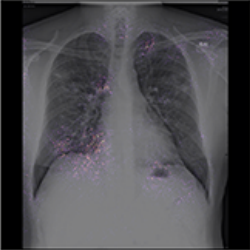

In the first example, in Figure 5a), the model focuses on clavicles, scapulas, and soft tissues, which are outside the lungs. Very likely, the model predicts illness based on an improper part of the image. Location of the areas marked by explanation should be inside the chest on the lung tissue because COVID/̄19 lesions are not located on, e.g., lymph nodes. Moreover, there are some elements that cannot be considered as decision factors like imaging artifacts (cables, breathing tubes, image compression) or embedded markup symbols [37]. To prevent the model from focusing on irrelevant features, in some studies, the lungs were segmented, and their background was removed [31, 32, 34, 45, 50]. However, it may not help when some imaging artifacts are present in the area of the lungs.